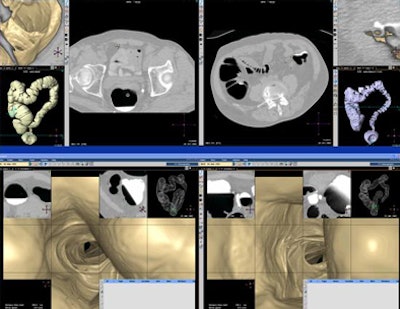

![]() |

| Primary 3D (bottom) interpretation of CTC data may deliver greater sensitivity than primary 2D reading for trained but less experienced readers. All images courtesy of Dr. Ayso de Vries. |